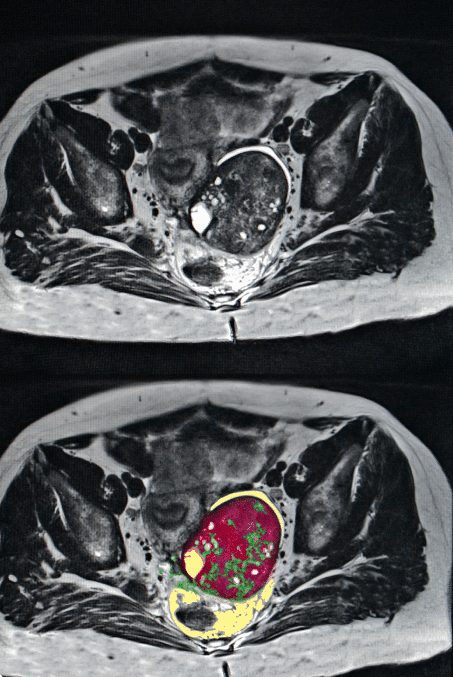

Peritoneal Mesothelioma Misdiagnosis

The symptoms of peritoneal mesothelioma are nonspecific and difficult to diagnose. The most common symptom is a distended abdomen, occurring in 30 to 80 percent of patients, according to the Annals of Translational Medicine. The second most common complaint is nonspecific abdominal pain, occurring in 27 to 58 percent of peritoneal mesothelioma patients.

Ovarian mesothelioma is very rare, and it is difficult to differentiate from ovarian cancer and peritoneal mesothelioma. Ovarian mesothelioma may spread to the peritoneum before mesothelioma is diagnosed. Additionally, ovarian cancer and mesothelioma have similar properties on radiological tests, and the cells of both types look similar when viewed under a microscope.

This similarity means ovarian mesothelioma may be misdiagnosed as peritoneal mesothelioma or ovarian cancer. Misdiagnosing ovarian mesothelioma can lead to underestimation of the tumor, resulting in less effective or less targeted treatment.

The diagnosis of ovarian mesothelioma should be confirmed via immunohistochemical staining. This is the most reliable means to distinguish ovarian mesothelioma cells from ovarian cancer cells.